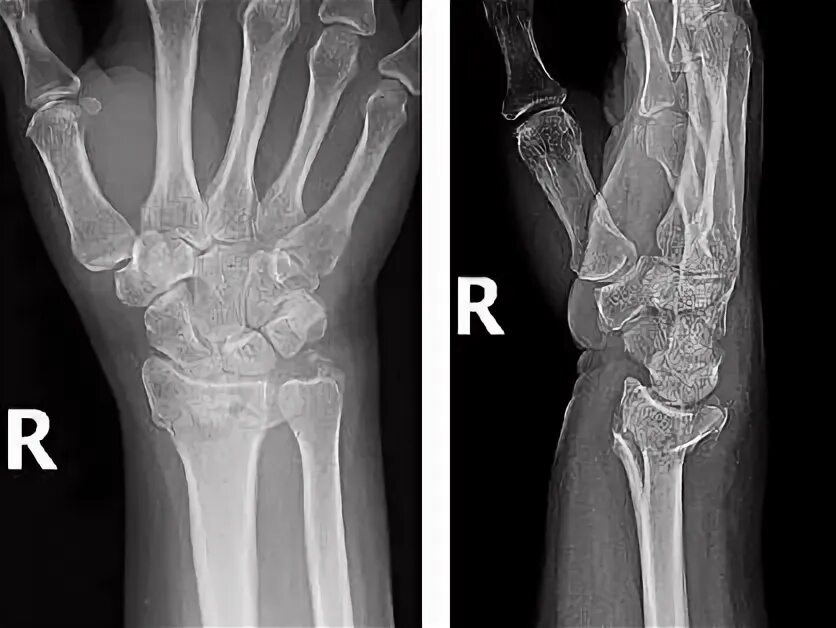

Мкб перелом луча в типичном